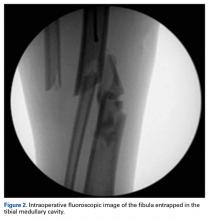

Immediate closed reduction was performed in the emergency department, with the patient under sedation. The procedure improved gross realignment and reduced tension from the overlying soft tissue. Postreduction radiographs showed improved alignment that, with some displacement and angulation remaining, was deemed sufficient to temporize the injury until surgery the next morning.The next morning, the patient was taken to the operating room for planned closed intramedullary nailing through a suprapatellar approach. After entry to the tibial medullary canal was obtained, a ball-tipped guide wire was advanced proximal to the fracture site, until significant resistance was met. With the aid of intraoperative fluoroscopic imaging, it was determined that the distal fibula fracture segment was entrapped in the medullary canal of the proximal tibia (Figure 2).